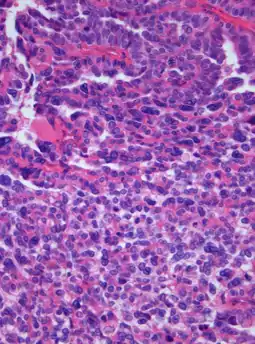

Photomicrograph of hematoxylin-eosin stained section of a choroid plexus carcinoma (grade III WHO) at 400x magnification.

A choroid plexus carcinoma (WHO grade III) is a type of choroid plexus tumor[1] that affects the choroid plexus of the brain. It is considered the worst of the three grades of chord plexus tumors, having a much poorer prognosis than choroid atypical plexus papilloma (WHO grade II) and choroid plexus papilloma (WHO grade I).[2] The disease creates lesions in the brain and increases cerebrospinal fluid volume, resulting in hydrocephalus.[3]